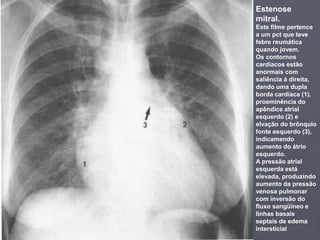

Estenose

mitral.

Este filme pertence

a um pct que teve

febre reumática

quando jovem.

Os contornos

cardíacos estão

anormais com

saliência à direita,

dando uma dupla

borda cardíaca (1),

proeminência do

apêndice atrial

esquerdo (2) e

elvação do brônquio

fonte esquerdo (3),

indicamendo

aumento do átrio

esquerdo.

A pressão atrial

esquerda está

elevada, produzindo

aumento da pressão

venosa pulmonar

com inversão do

fluxo sangüíneo e

linhas basais

septais de edema

intersticial